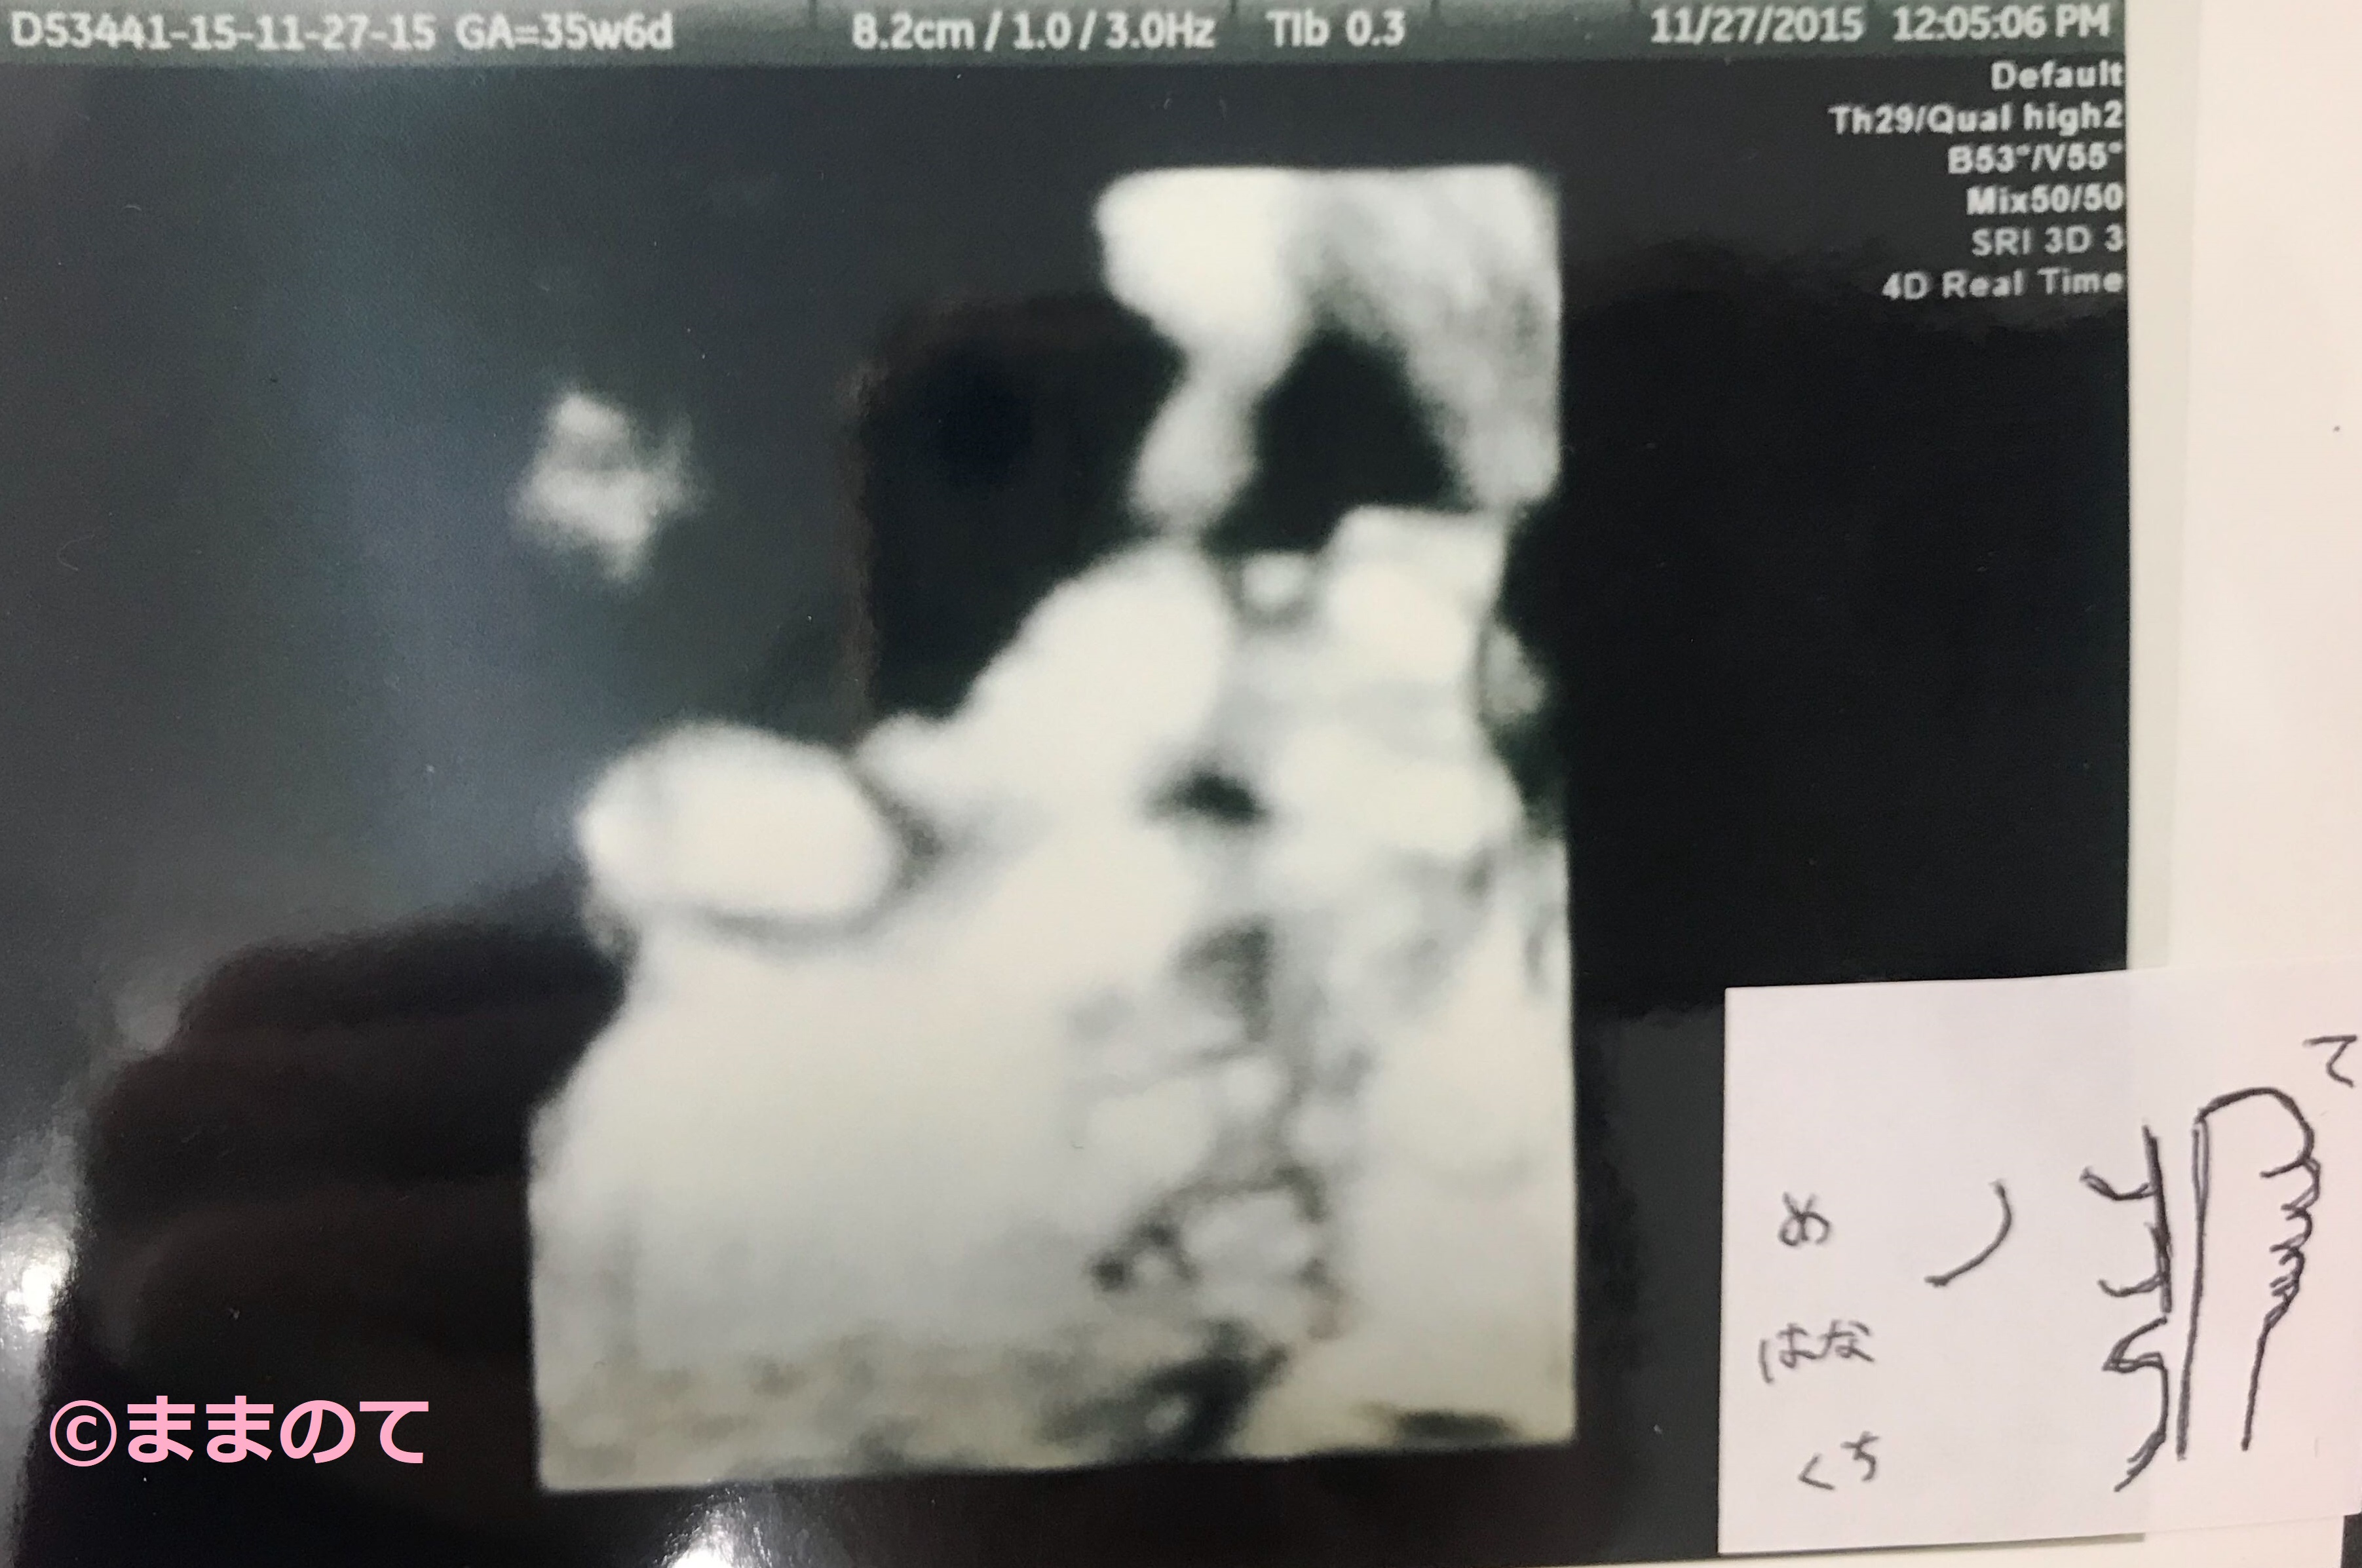

妊娠35週の赤ちゃんのエコー画像

皮下脂肪がついて顔も身体もふっくらし、新生児とほぼ同じ外見になってきました。髪が伸び、爪も指の先端まで覆うころです。体重や体形に差が出てくるころなので、赤ちゃんの個性が見られるとママも嬉しくなりますね。かわいらしさだけではなく、たくましさが出てきた赤ちゃんの姿をエコーでも確認できるでしょう。上の写真は妊娠35週6日の4Dエコーの写真です。顔のパーツや肉付きがしっかり確認できますね。